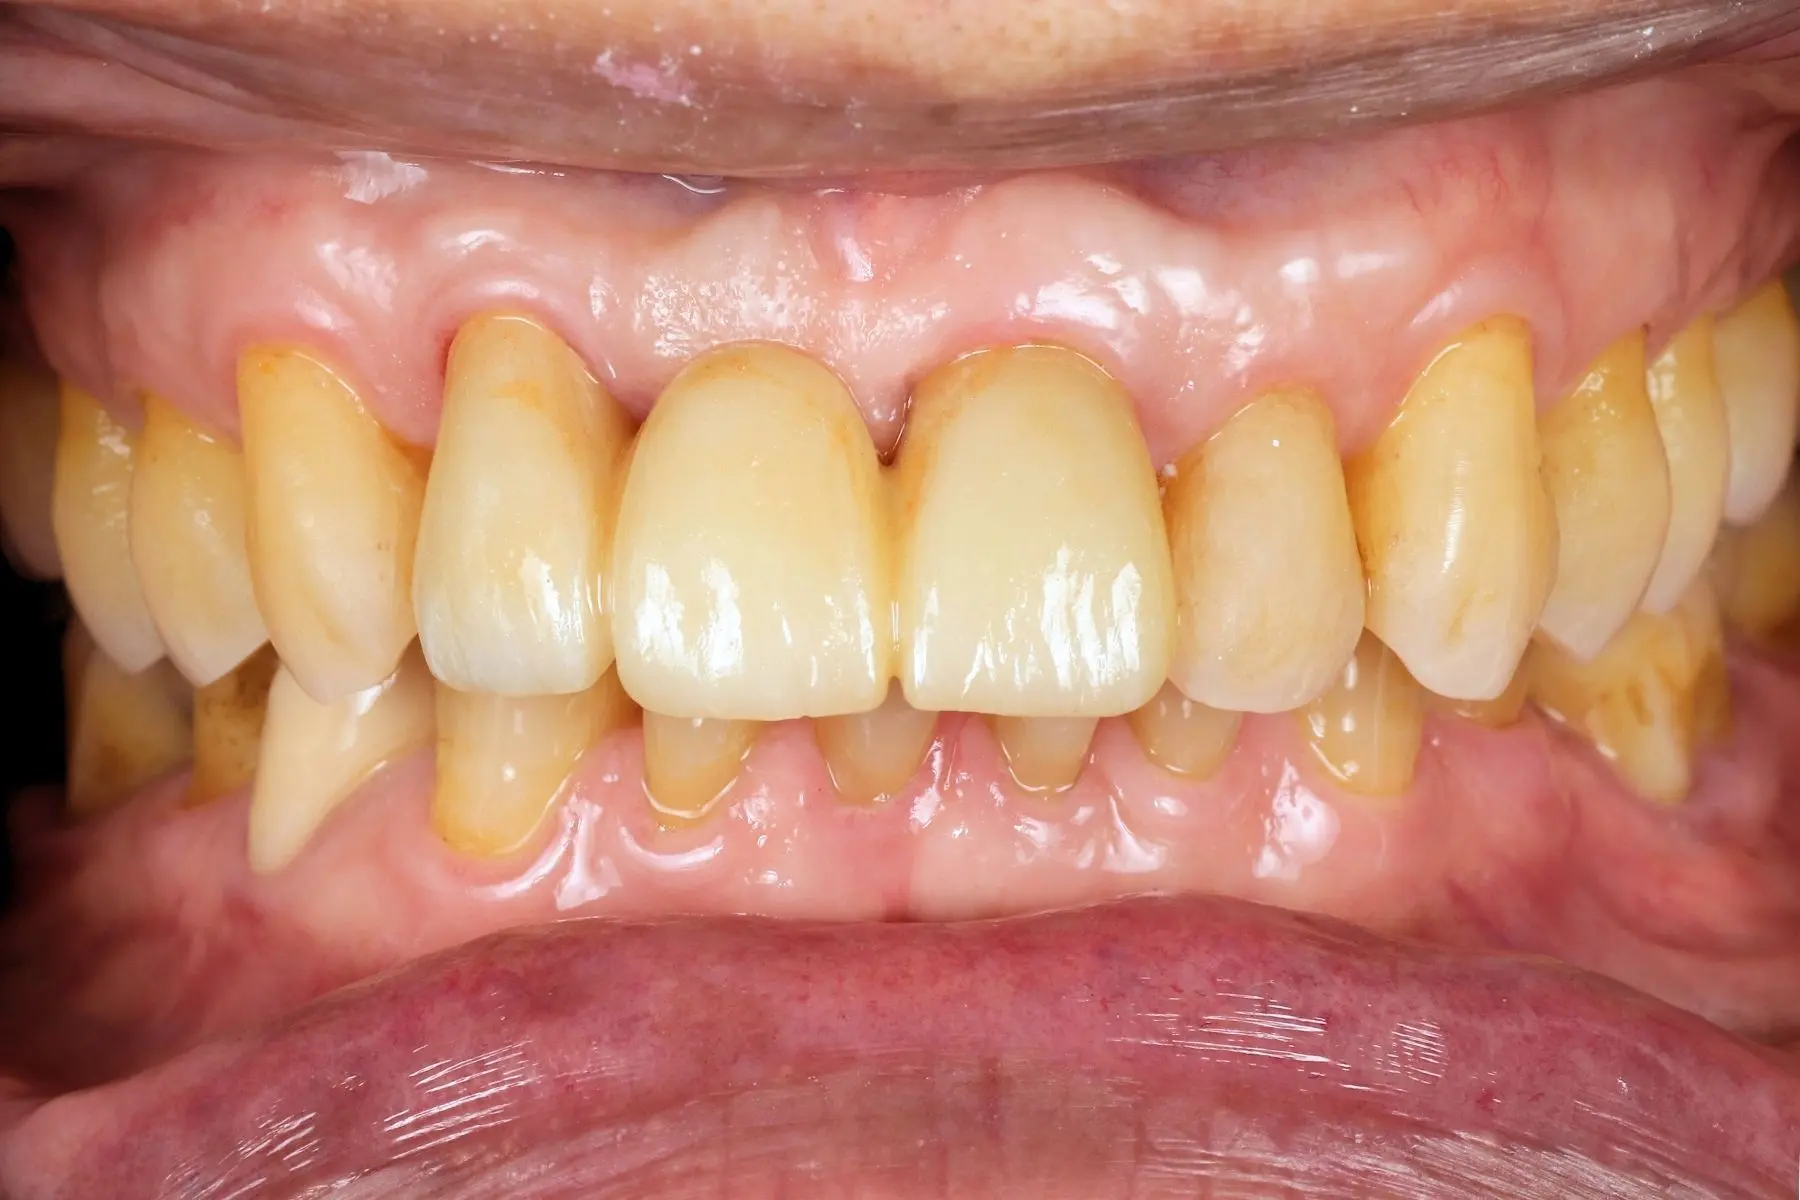

主訴

右上前牙牙齦反覆腫脹化膿

• 術前 41

術後 39

仿生美學樹脂

主治醫師

• 陳暐文

治療時間

單次療程

左上門牙因撞擊出現缺角,希望修復自然外觀、不想看出補過痕跡